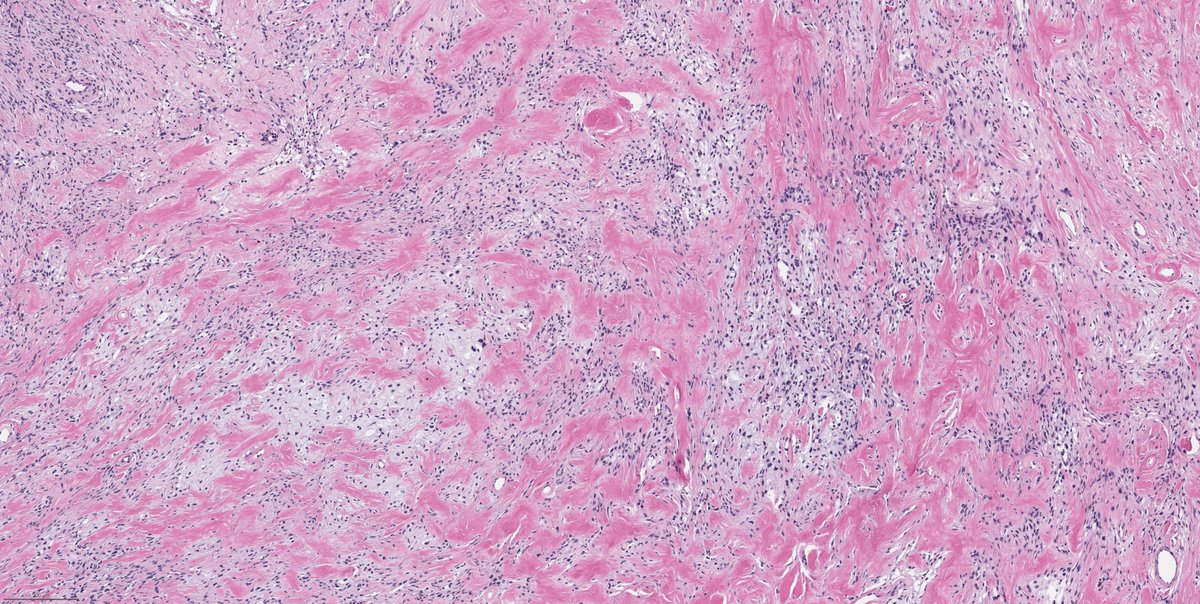

Liver lesion. Adult. Diagnosis anyone? #GIpath @MGHPathology

11

62

140